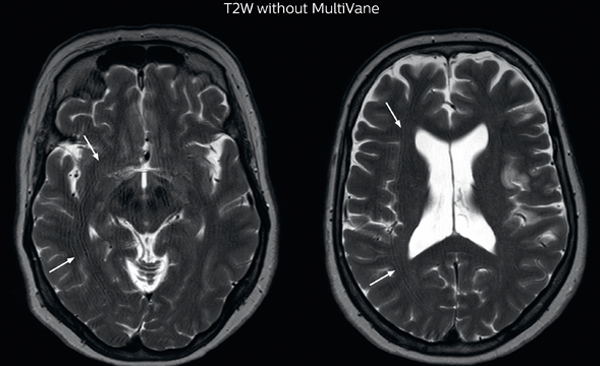

“Motion artifacts can obscure subtle findings, make image interpretation more difficult and decrease diagnosis confidence. For example, when imaging the cerebellum or brain stem, or when looking for subtle multiple sclerosis (MS) lesions, motion can be problematic,” says Dr Nickerson. MultiVane XD motion-free imaging delivers diagnostic images even in the case of severe patient motion. A more relevant patient group is one with typical small artifacts related to moderate motion like an occasional cough. The absence of those artefacts brings forth better day-to-day diagnostic confidence. MultiVane XD works in multiple orientations and for various contrasts, such as T1-weighted, T2 weighted and FLAIR. Trevor Andrews, PhD, explains that the team compared motion artifacts seen in the brain with MultiVane XD and with T2-weighted TSE. “In nine out of the ten datasets in our studywe saw clear improvementswith MultiVane XD, while in the tenth dataset image qualitywas comparable. The MultiVane XD sequence is now used in the majority of patients that present at UVM for brain MRI.”

“We saw MultiVane XD provide remarkable improvement, not only for artifacts caused by patient motion, but also for the extent of pulsation artifacts in the basal cisterns. Based on these results, we have added the MultiVane XD sequence to our brain studies,” says Dr. Nickerson. “MultiVane XD is especially useful when imaging patients with diseases that cause white matter changes on T2-weighted images, such as MS, small vessel disease, vasculitis and sarcoidosis,” says Dr. Nickerson. “Many of these are only visible on T2-weighted or FLAIR images, and sometimes aren’t even seen with FLAIR images. However, when using MultiVane XD and we don’t see any motion on the rest of the scan, but still do see a signal abnormality, we can probably attribute that to a real disease process, rather than an artifact.”

The images made with MultiVane XD show significant reduction in motion artifact compared to the T2-weighted images without MultiVane below them. Scanned on Ingenia 3.0T